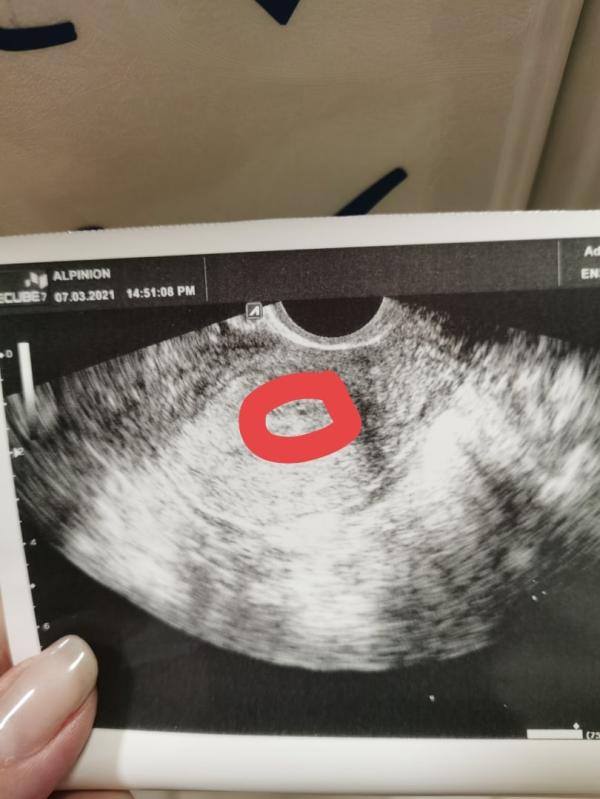

На память мой маленький малыш 🙁и замер на 5,5 неделе. Фото с узи буквально за 5 дней было сделано. Эх... Идём дальше. Жизнь продолжается, всем спасибо, кто поддерживал 🙏